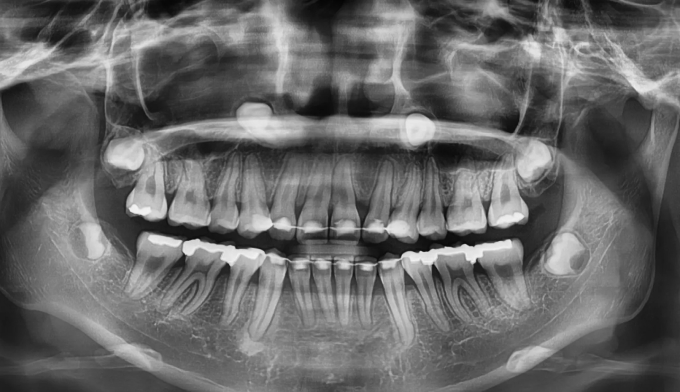

매복치의 경우 무조건 교정을 통해 구강내로 견인해야 하는건 아닙니다.

교정을 했을때의 득과 실을 살펴보는것이 중요합니다. 너무 깊숙히 묻혀있는 치아는 그냥 놔두는것이 나을때도 있습니다.

위쪽 송곳니가 엑스레이상에서도 거의 코 옆쪽으로 매복되어 있는 케이스입니다.

매복치에 접근하는것이 무리라고 판단되어 유치만 발치하고 진행하기로 하였습니다.

아래치아도 갯수를 맞춰주기위해 하나씩 발치하였습니다.